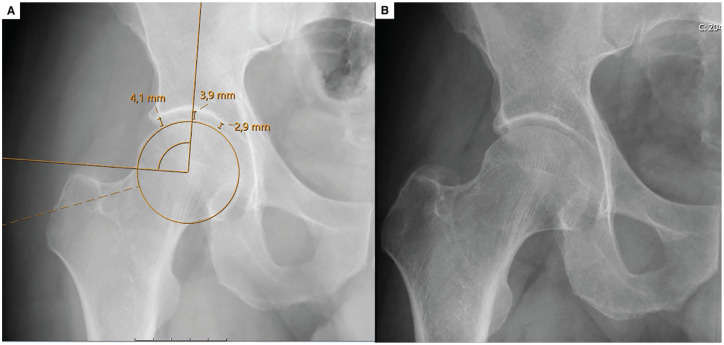

Methods: Patients who had primary hip arthroscopy for FAI between February 5, 2013, and June 1, 2022, with a minimum 2-year follow-up, were included and categorized into 2 age groups (≥35 years and <35 years). Radiographic measurements of JSW on plain anteroposterior pelvic radiographs were used to calculate L/M and C/M ratios. Patient-reported outcomes included the modified Harris Hip Score (mHHS) and visual analog scale for pain. Statistical analysis included chi-square, Mann-Whitney U, and Wilcoxon tests to compare categorical and continuous variables. The receiver operating characteristic (ROC) curve and area under the curve (AUC) assessed threshold values for L/M and C/M ratios predicting the Patient Acceptable Symptom State (PASS) for mHHS at 2 years.

Results: A total of 110 patients (114 hips) were identified, comprising 56 hips from the older group (age ≥35 years) and 58 hips from the younger group (age <35 years). The ROC curve for preoperative C/M effectively distinguished between patients who achieved and did not achieve a second-year PASS value, with an AUC of 0.70 in older patients. Older patients, compared with younger, demonstrated lower postoperative mHHS (89 ± 10 vs 94 ± 8; P = .01) but similar rates of PASS achievement (75% vs 88%; P = .07). The C/M ratio was a significant predictor of functional outcomes in patients aged ≥35. Patients with a preoperative C/M ratio ≥1.08 achieved significantly better outcomes. No significant predictive value was found for L/M ratios in older patients or for L/M and C/M ratios in younger patients.